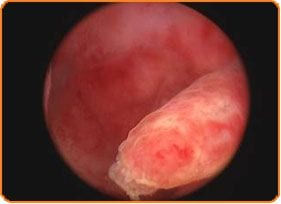

Die diagnostische Hysteroskopie wird so sehr schnell und schmerzlos durchgeführt wie ein Besuch zum Pap-Abstrich-Test. Gleichzeitig wird sie auf Video aufgezeichnet. Das Innere der Gebärmutter, der Embryoimplantationsort, stellt heute eine operativ gut zugängliche Region dar. Die Untersuchung erfolgt mit direkter Sicht mit dem Hysteroskop, liefert wichtige Informationen über die Faktoren erniedrigter Fruchtbarkeit, wie z.B.:

- die Qualität des Endometriums

- die Präsenz von Polypen

- die Präsenz von Narben oder weiteren entzündeten Elementen.

Die operative Hysteroskopie stellt eine weitere moderne Option unseres Zentrums dar. Sie erfordert eine Anästhesie und sollte deshalb einem sicheren Ort durchgeführt werden, wie in der Klinik des „Mitosis“-Zentrums. In diesem Prozess können wir sicher, komplikationslos und vor allem in einer sehr kurzen Zeit Operation durchführen, Deformationsfaktoren der Gebärmutterhöhle behandeln, Schwangerschaftsverhütung vornehmen aber auch bei Fehlgeburten eingreifen, wie z.B.:

- Entfernung von Polypen